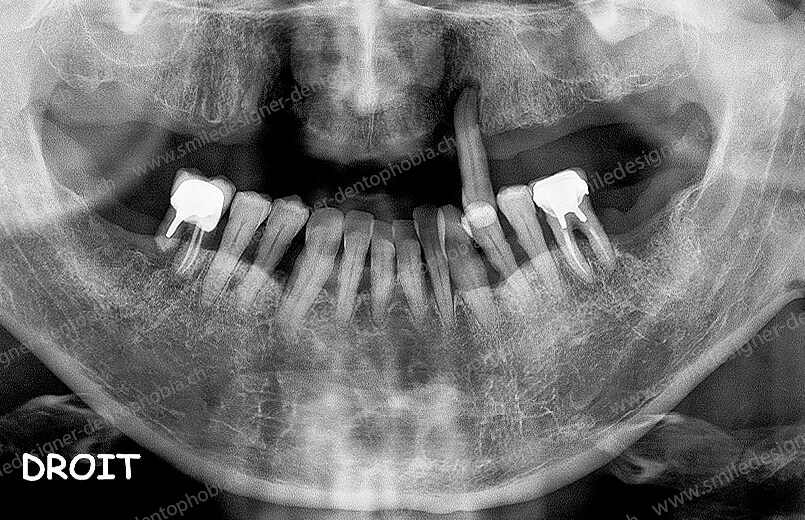

Cas clinique « DOMINO SURGERIES MCI » : Bridge implanto-porté sans extension postérieure (ALL ON 10/8). Version définitive des bridges avec un cosmétique en céramique. Double comblements de sinus et double greffes osseuses d’apposition pour la reconstruction du maxillaire.

Cas clinique « DOMINO SURGERIES MCI » : Bridge implanto-porté sans extension postérieure (ALL ON 8/6). Version définitive des bridges avec un cosmétique en céramique. Double comblements de sinus et double greffes osseuses d’apposition pour la reconstruction du maxillaire.

Cas clinique « DOMINO SURGERIES MCI » : Bridge implanto-porté avec extensions postérieures (ALL ON 6/6).

Version intermédiaire des bridges de première intention de Mise en Charge Immédiate (MCI) pour une resocialisation immédiate de la patiente cas en cours de cicatrisation des sinus lift et en attente des futurs implants postérieurs maxillaires.

Version définitive des bridges avec un cosmétique en céramique (ALL ON 10/6). Double comblements de sinus et double greffes osseuses d’apposition pour la reconstruction du maxillaire.

- Deuxième étape : une série de greffes osseuses (sinus lift, greffes d’apposition, etc.) pour reconstruire les secteurs postérieurs, en attendant la cicatrisation entre chaque intervention.